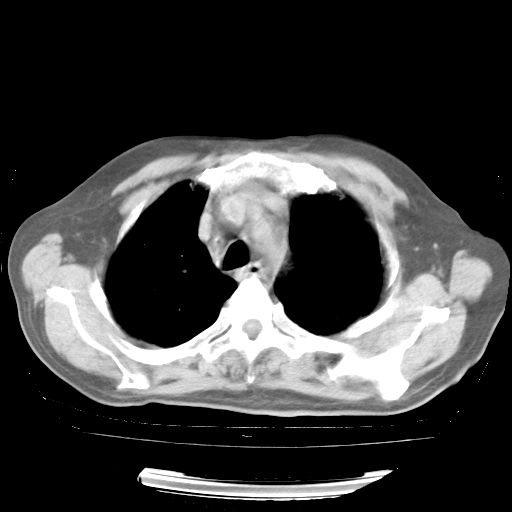

4月28日肺部CT——再次出现类似去年5月9日——透光度降低,“间质性”改变。

4月28日肺部CT——再次出现类似去年5月9日——磨玻璃样、间有“粟粒样”改变。

4月28日肺部CT

个人阅读4.14日肺部CT平扫:纵隔窗无异常,但肺窗示:双下肺内、后基底段有片絮状侵润影,部位以后基底段为著,以间质改变为主,呈急性肺泡炎征像,和首次住院影像学有相似之处。仅是个人读片,明日请相关专家再读片哈。其它建议同上。